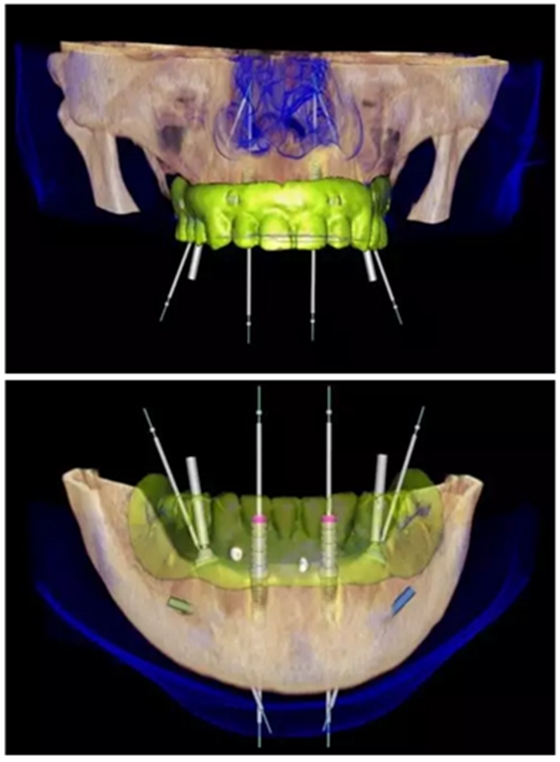

數(shù)字化治療方案設(shè)計

使用NobelClinician針對上頜及下頜分別進(jìn)行數(shù)字化的種植修復(fù)方案設(shè)計。